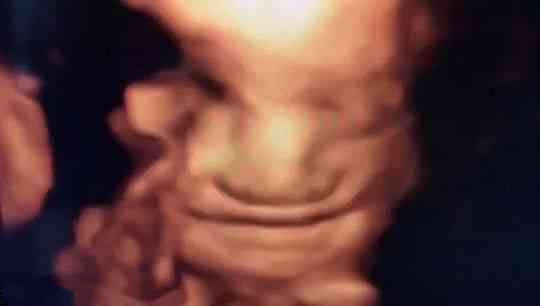

苗苗怀孕5个半月的时候去做四维彩超,她一直注视着大屏幕上宝宝的一举一动。忽然,她看到胎宝宝咧嘴笑了,这给她大大的惊喜,同时,她又很惊讶,宝宝在肚子里也会笑?常听说宝宝出生后还不会笑呢?

医生说:很正常,我们做四维彩超经常看到有宝宝笑。苗苗才知道自己是少见多怪了,而医生见的多了觉得稀松平常。

怀孕5个半月,胎儿已经有了面部表情,喜怒哀乐都会有,当然胎儿也会发笑。

5个半月的胎儿相当于22周,眼睛、鼻子、眉毛、耳朵、嘴巴等五官面貌结构完整,嘴巴、眉毛活动自如,面部表情丰富也很正常。

从这里看出,在做四维彩超的时候很容易捕捉到胎儿的微笑,这时不要觉得奇怪,这是胎儿正常的生理反应。